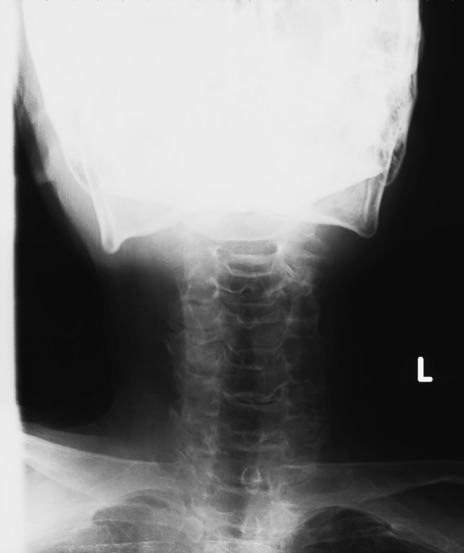

症例48 頚椎レントゲン(正面像)

【症例】80歳代女性

【主訴】頸部痛

【現病歴】昨日家の階段を2段くらい上がったところで転倒して受傷。

異常所見と診断は?